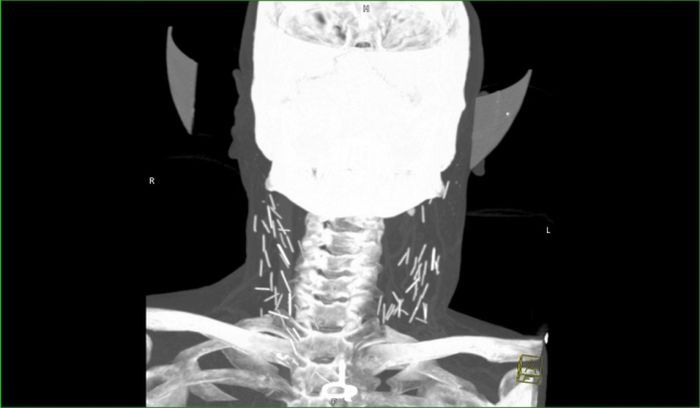

Рентген показал, что у чувака в шее огромное количество иголок.

Оказалось, что товарищ - нарк со стажем и все эти иглы остались в шее после неаккуратных инъекций.

Парня подлечили, конечно. Но иглы он отказался вытаскивать, так как он их типа любит и привык к ним.